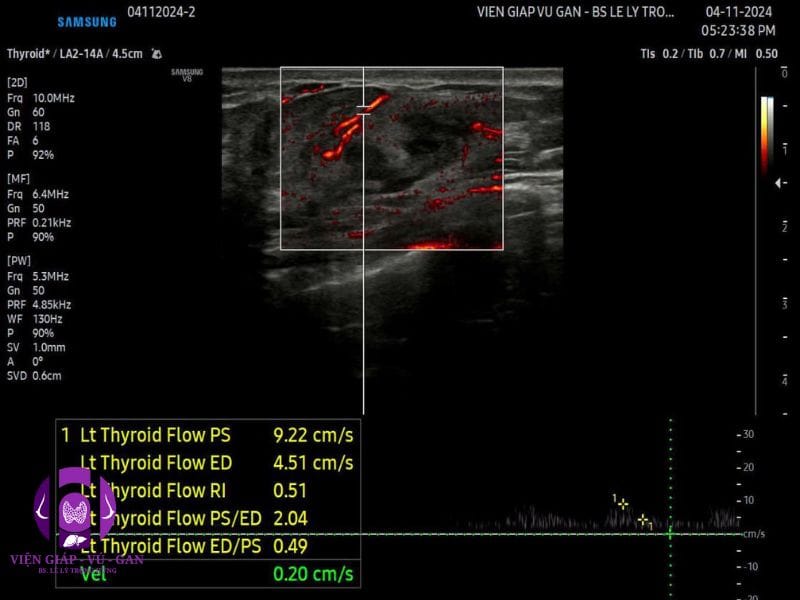

- Vú trái: vị trí 7 g cách núm vú 3 cm có khối đặc,echo kém, không đồng nhất, hình bầu dục, bờ đều, giới hạn rõ, không vôi, kích thước 23x20x10mm . Doppler: mạch máu phân bố dạng vòng , V = 9cm/s, RI =0,5. SWE = 19kPa.